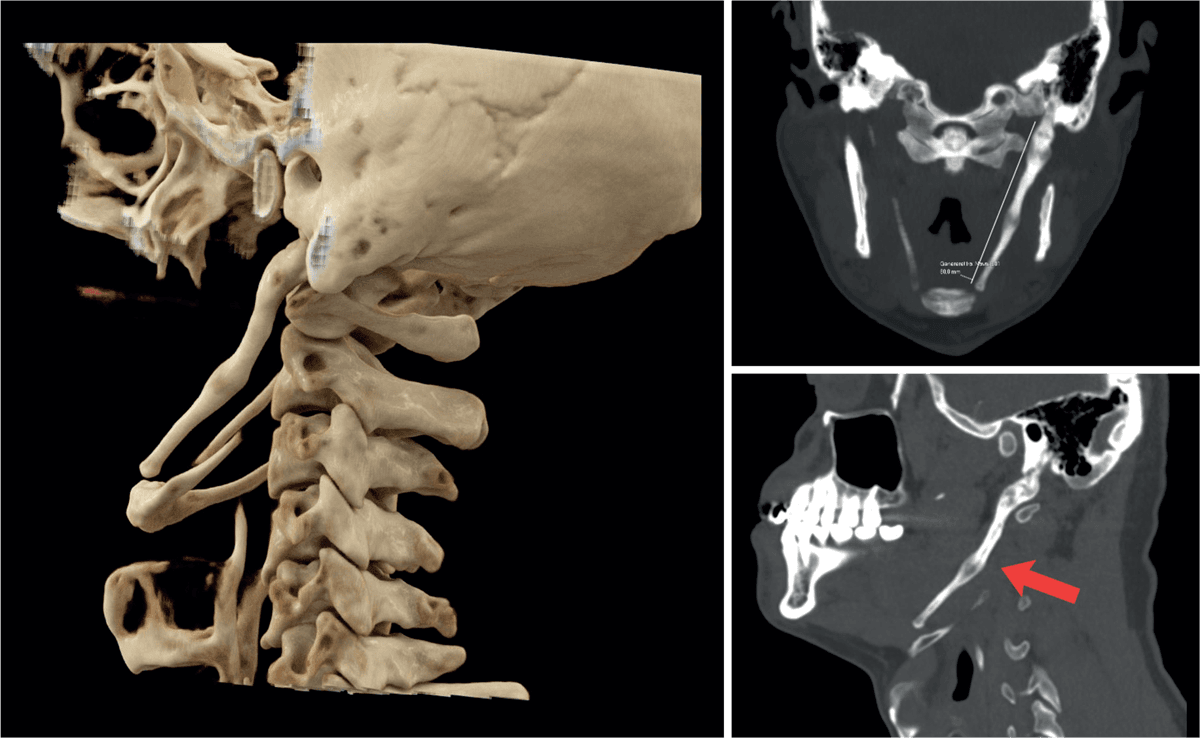

En 54-årig mand blev henvist med tre års intermitterende smerter, dysfagi og muskelspændinger lokaliseret til venstre kæbevinkel og strube. Smerterne forværredes eller opstod ved gab eller grin, og patienten kunne opleve en knasen ved hovedbevægelser. Han havde prøvet talepædagog og kraniosakralterapi uden effekt. Ved en otologisk undersøgelse var det eneste abnorme fund en palpatorisk markant processus styloideus i venstre side intraoralt.

På mistanke om Eagles syndrom blev der foretaget CT. Processus styloideus sinister var fortykket og nåede helt ned til os hyoideum, 8 cm lang. Da patienten kom til kontrol med svar på CT, gik det markant bedre, og han afstod fra operation.

Eagles syndrom er en symptomgivende, forlænget processus styloideus. En forlænget kalcificeret processus styloideus ses hos omkring 4% af befolkningen, men kun en brøkdel vil få gener heraf (4-10%) [1]. De klassiske symptomer kan være smerter i hals ved bevægelse af hoved eller kæbe, fremmedlegemefornemmelse, synkesmerter og otalgi [2]. Operativ fjernelse af processen kan give symptomlindring.